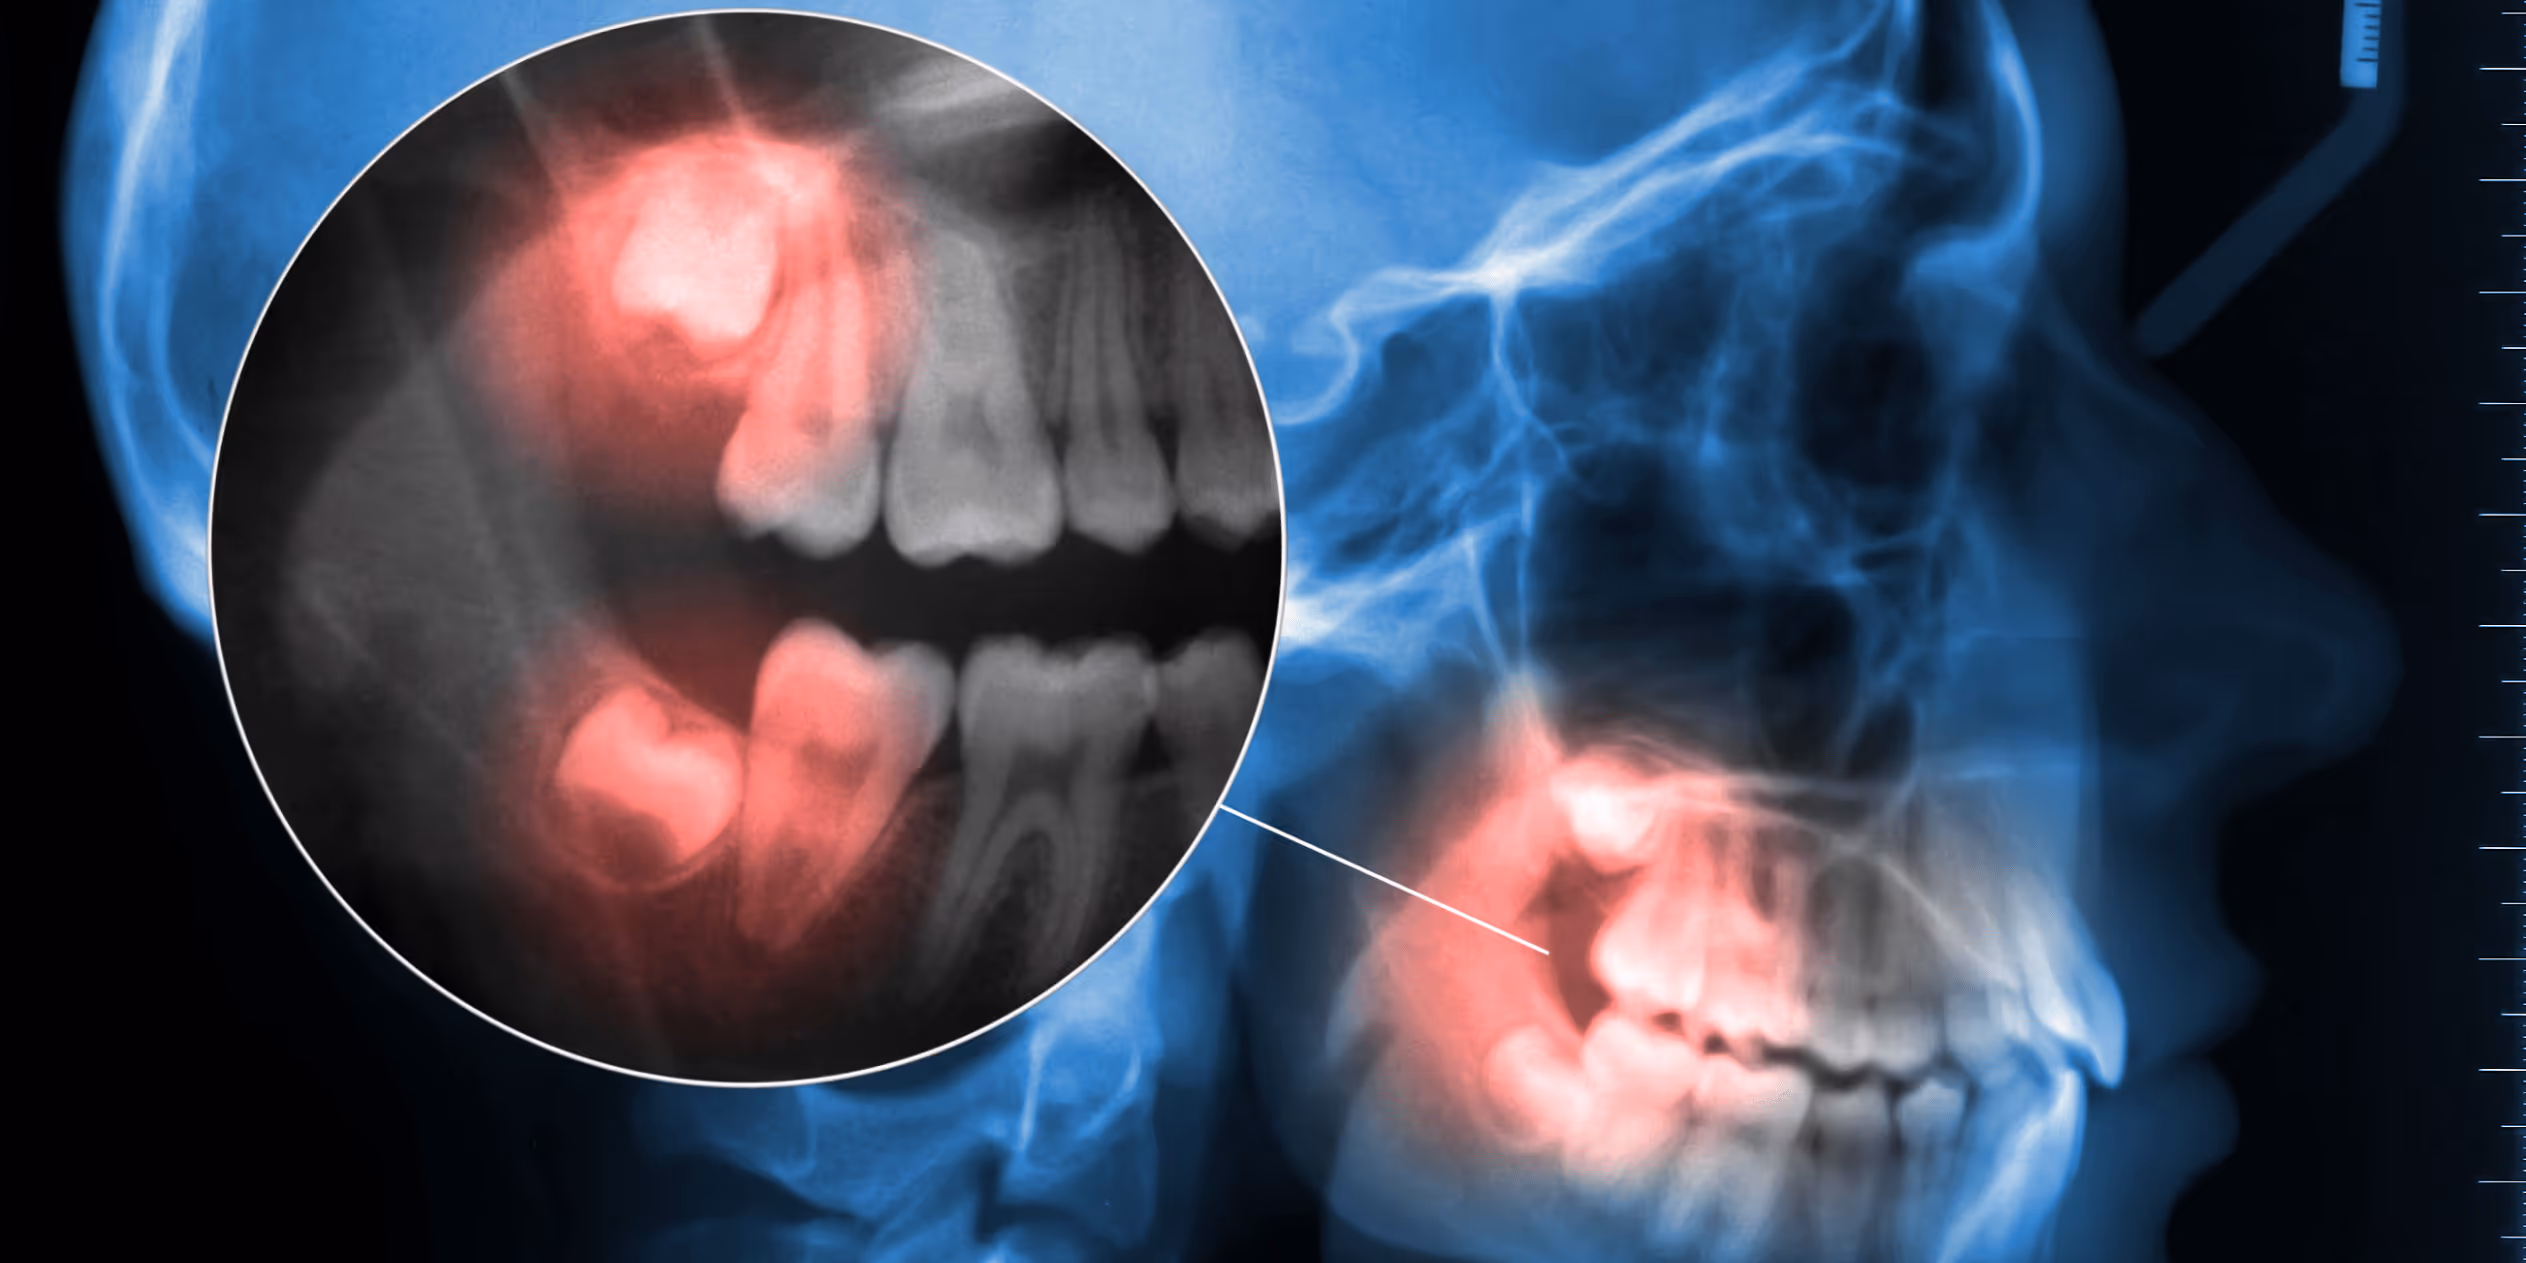

In vielen Fällen bleiben Weisheitszähne deshalb ganz oder teilweise im Kieferknochen verborgen – sogenannte retinierte Weisheitszähne. Andere wiederum brechen schief durch oder drücken auf die benachbarten Backenzähne. Solche Konstellationen können zu chronischen Entzündungen, Karies an angrenzenden Zähnen, Zystenbildung oder sogar Zahnverschiebungen führen.

Die Entscheidung zur Entfernung wird immer individuell und nach genauer Untersuchung getroffen. In der Ordination in Hollabrunn kommen dafür modernste bildgebende Verfahren wie digitale Volumentomographie (DVT) zum Einsatz, um die genaue Lage und Ausrichtung der Zähne sowie die Nähe zu empfindlichen Strukturen wie Nerven zu beurteilen.